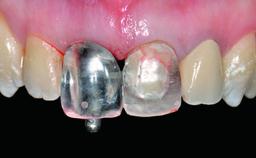

A 49-year-old female patient was referred for implant therapy to replace the upper right central incisor (tooth 11). The tooth had been assessed by an endodontist who diagnosed a vertical fracture of the root. The tooth had a hopeless prognosis and needed to be extracted. The patient was healthy and was not taking any medications. She was allergic to penicillin. The patient had high esthetic demands but her expectations were realistic. The extraoral examination revealed no facial asymmetries. The right temporomandibular joint demonstrated an opening click but was otherwise asymptomatic. The lip line was high with a significant gingival display.